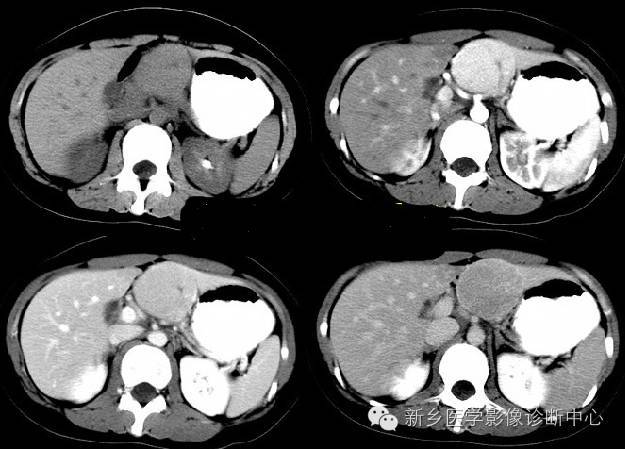

7、转移瘤

肝转移癌的CT表现因原发癌及病理组织类型不同而异。

平扫时:显示为多发性大小不等的低密度肿瘤结节,也可为单发结节。多在低密度内存在更低密度区域,从而显示为同心圆状或等高线状双重轮廓为其特征。

增强扫描:肿瘤境界清楚,边缘部分可增强而密度增高。1cm大小转移癌可出现类似环状增强的表现。

平滑肌肉瘤、软骨肉瘤、类癌、肾癌、胰岛素瘤、甲状腺癌等的肝转移癌血供丰富,动脉期及门脉期可见明显肿瘤增强征象。有时候与肝细胞癌难以鉴别,但其总体以环状增强为主要特征,再结合临床诊断很重要。